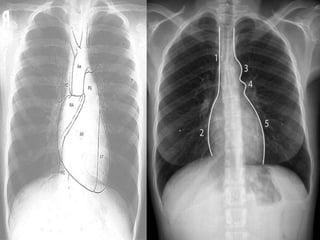

Radiological aspect

Through X-ray we can get to know the contour of

the heart and can find abnormalities of the heart

chambers and great vessels to some extent, most

commonly posteroanterior(PA) and lateral view

are employed.

Ultrasonography helps in measuring the various

dimensions of heart chambers, commonly

employed are 4-chamber apical view, subxiphoid

view, parasternal long axis and parasternal short

axis views.